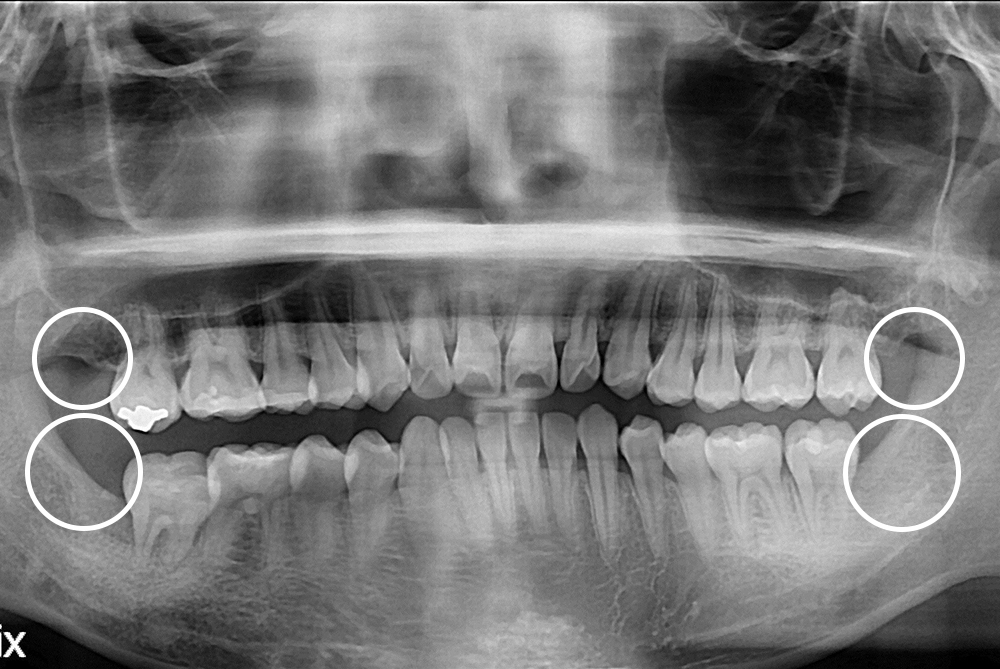

치료후 : 2019-10-25

세종치과는 구강악안면외과학 박사이신 원장님이 발치하는 치과입니다.